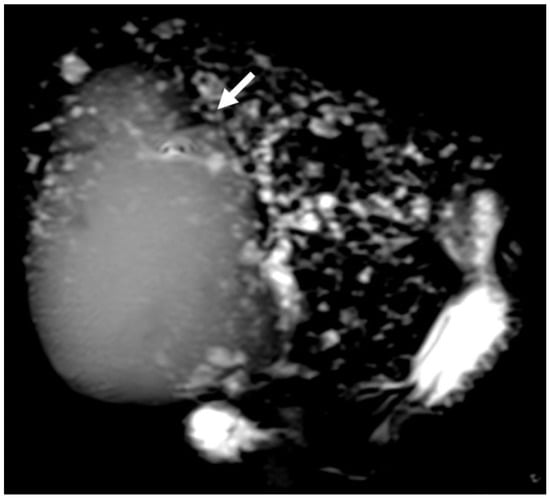

6.2. Intraductal Papillary Neoplasia of the Bile Duct

6.3. Intraductal Tubulopapillary Neoplasms of the Bile Duct

6.4. Hepatobiliary Mucinous Cystic Neoplasm